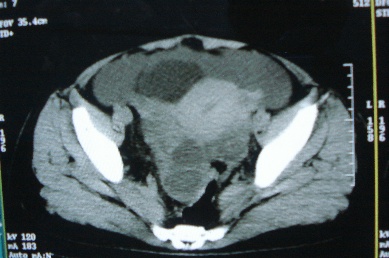

ct10755,女,48岁。感腹胀一周入院。

考虑右侧卵巢囊腺癌并腹腔转移、子宫肌瘤

感觉像是2个病变融合:双侧附件囊腺瘤?

考虑右侧卵巢囊腺癌并腹腔转移可能性大、子宫肌瘤

支持:右侧卵巢囊腺癌并腹腔转移,或囊腺瘤破裂腹腔种植。

支持:右侧卵巢囊腺癌并腹腔转移、腹水、盆腔积液。